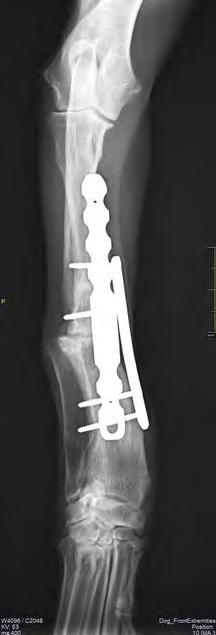

Después de la cirugía se analizaron las radiografías postoperatorias, realizándose las mismas mediciones que en la planificación, y observándose cómo los valores obtenidos tras la cirugía se correspondían con los valores planificados (Fig. 5). Se colocó un vendaje postoperatorio sencillo durante 14 días, para evitar la manipulación del área quirúrgica por parte de la pa-

Figura 5. Proyecciones radiográficas craneocaudal y mediolateral posquirúrgicas. Las radiografías muestran el resultado tras la cirugía.